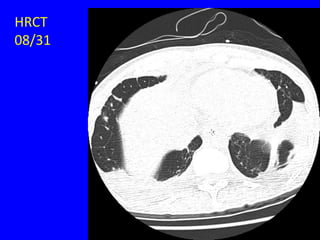

HRCT

08/31

Notes

• The previous slide shows CT taken

during inspiration.

• Usually, a blood vessel has a

bronchus beside it that has the same

size.

• So, if you see a bronchus larger than

the accompanied vessel then suspect

bronchiectasis.